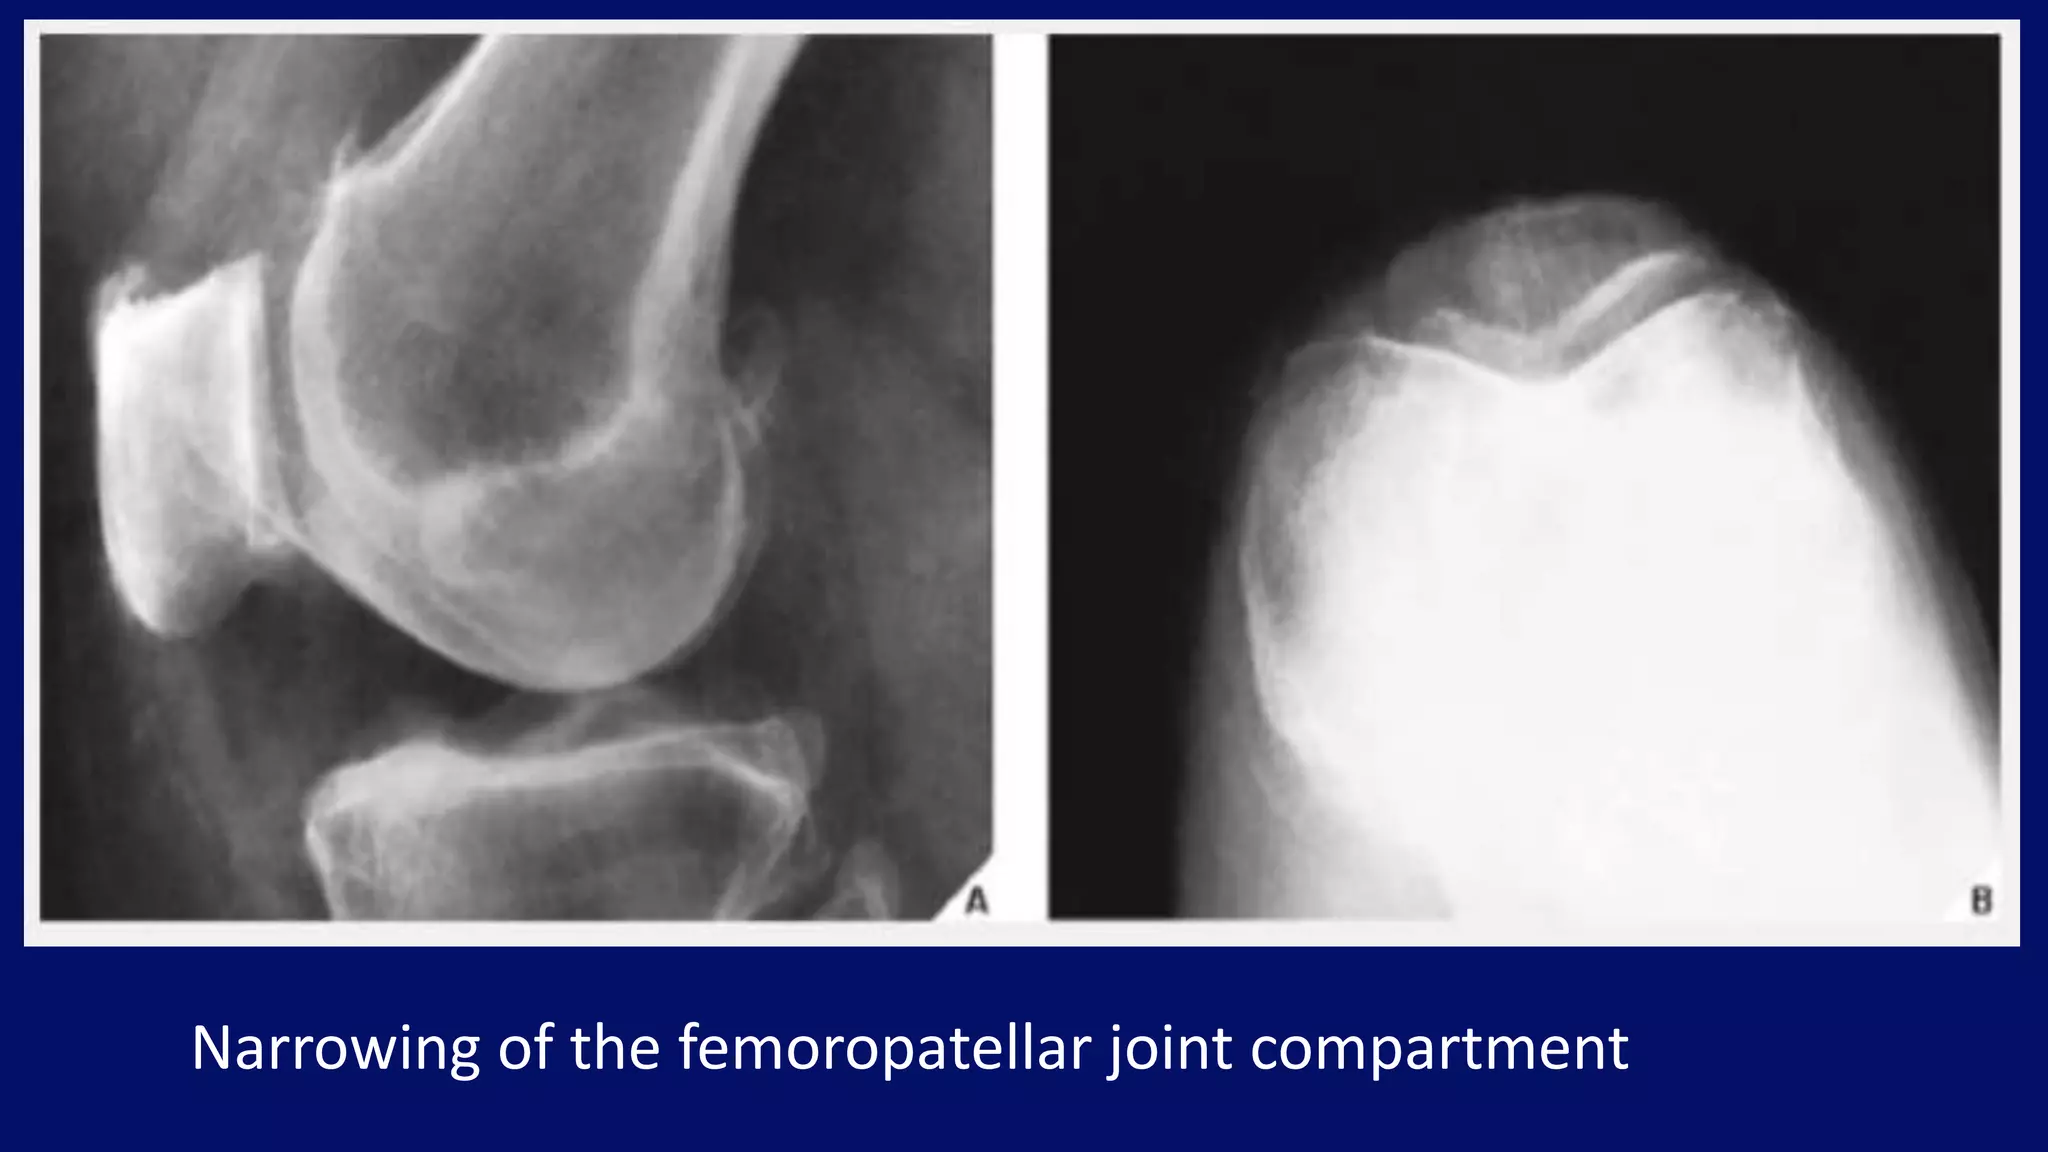

Narrowing of the femoropatellar joint compartment

• #27 Lateral radiograph of the knee (A) and axial radiograph of the patella (B) of a 72-year-old woman demonstrate narrowing of the medial femoropatellar joint compartment and osteophyte formation on the medial aspect of the joint.